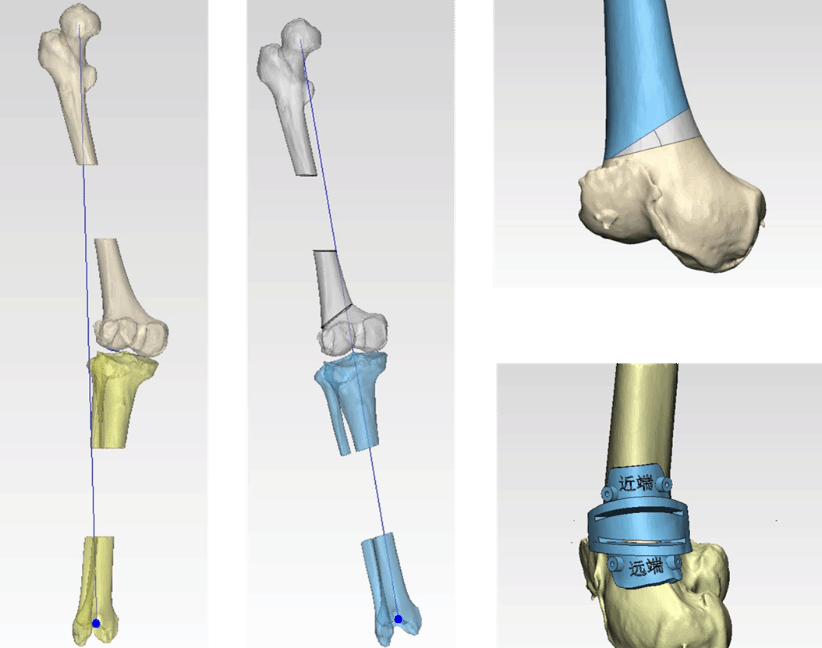

患者为57岁女性,因外伤导致右膝关节畸形40余年,严重影响了日常生活。经多方求医后,患者慕名前来我院运动医学科就诊,入院后科室高度重视,在党晓谦主任的指导下,时志斌教授、倪建龙副教授团队经过详细的术前检查与评估,为其制定个性化的手术治疗方案,通过对患者膝关节影像数据的分析,团队利用3D打印技术定制了符合患者个体解剖特点的截骨导板,从而实现股骨矫正的高度准确性,减少了传统手术中可能出现的误差,确保了股骨矫正后的关节功能得以最大程度恢复。

在截骨过程中,团队依据截骨导板,精准控制合页点位置和截骨角度,动态调整下肢力线至正常范围。为患者提供了个性化的力线矫正和功能改善保障。而对于外侧盘状半月板体部靠近滑膜缘的撕裂,在关节镜下通过Inside-out技术缝合两针,Outside-in技术缝合一针,修复了半月板的损伤。